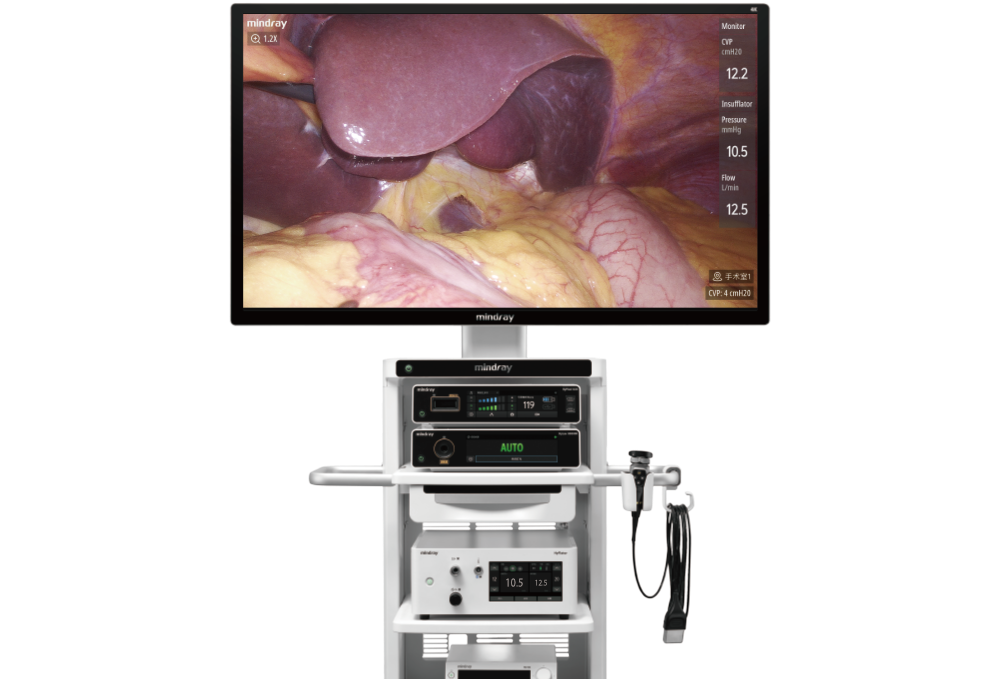

Data Sharing

The patient's vital signs data can be customized and displayed on the endoscope screen, allowing the surgeon to evaluate them timely during surgery. Displaying real-time pressure and flow volume of insufflation enhances surgical safety, efficiency, and education, ultimately contributing to better patient outcomes.

Digital OR, Upgraded Management

The UX7 Endoscope Camera System can be integrated into the Mindray digital operating room for centralized information management, enhancing the overall quality and efficiency of surgical procedures.